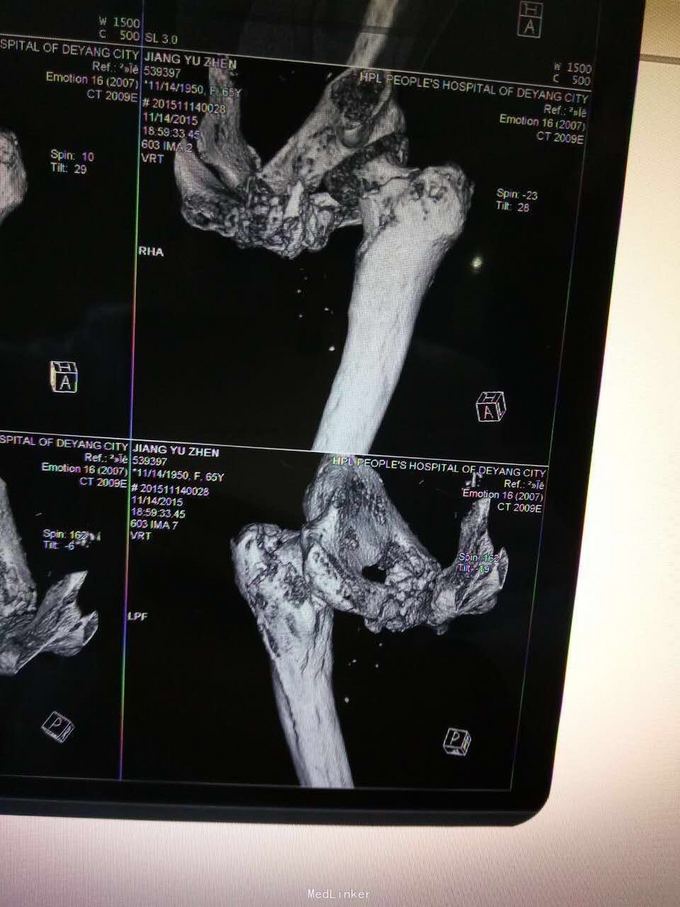

查体,左下肢外旋畸形,髋部压痛,轴向叩击痛。 x片提示:左股骨颈、转子间骨折,左股骨耻骨上支,耻骨联合、下肢粉碎性骨折。

诊断:左股骨颈、转子间粉碎性骨折,左耻骨上支、耻骨联合、下支粉碎性骨折,重度骨质疏松症, 处理:患肢制动,牵引,注射鲑降钙素,科室讨论意见为行髋关节置换术,与换方沟通后,换方表示拒绝手术治疗,主动出院。